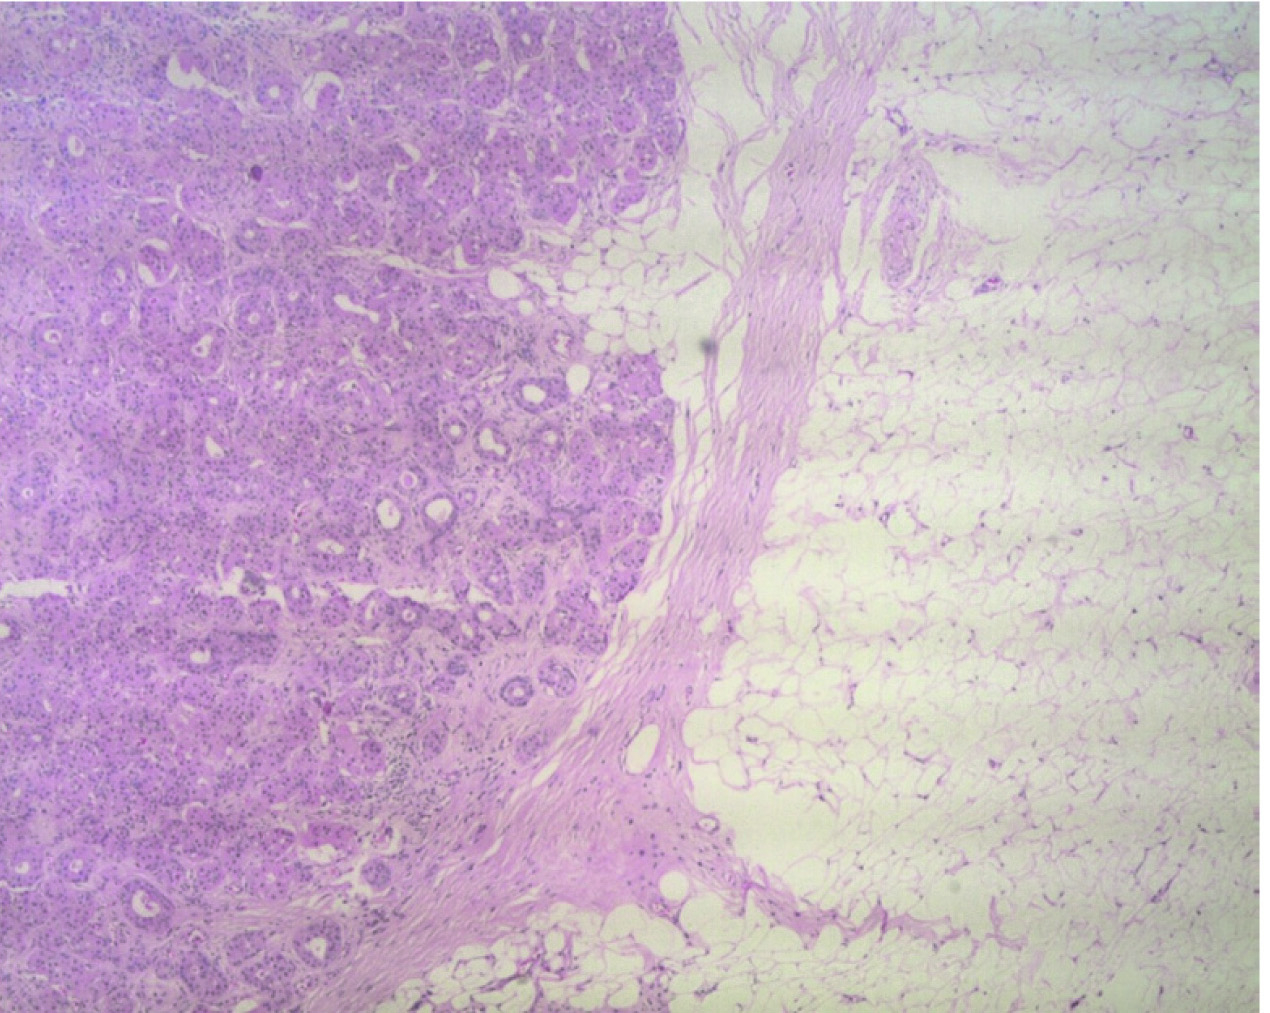

Left salivary gland was enlarged with a large fatty lesion, 55mm x 45mm x 20mm, having a large mural component. Lesion had solid component in it measuring approximately 27 x 17 mm. with a few mottled densities [Table/Fig-1]. There was no significant lymphadenopathy. Surgery was done under general anaesthesia. Patient was positioned on a shoulder roll with head tilted to right side. Painting with betadine lotion was done followed by drapping. The incision was made in the skin crease 5cm below the angle of mandible and deepened through platysma. Both superficial and deep lobes were identified with preservation of mandibular nerve and hypoglossal nerve with ligation of facial artery and facial vein. A 5 × 5 cm large mass arising from the left submandibular gland was excised and submitted for histopathological examination. After securing complete hemostasis, cervical fascia and skin flaps were sutured back in position. Grossly, the tumour was lobulated, encapsulated mass with well-defined brown areas and adjacent greasy-yellow soft areas [Table/Fig-2]. Histopathology examination revealed circumscribed tumour composed of lobules and sheets of oncocytes [Table/Fig-3,4]. Also, present were sheets and lobules of mature adipocytes, some of which are entrapped by the oncocytic nodules [Table/Fig-3,4]. There was patchy periductal chronic inflammation and fibrosis. There was focal sebaceous metaplasia at the edges of oncocytic nodules [Table/Fig-5]. There was no evidence of lymphovascular or perineurial invasion or any extra capsular invasion. Immunohistochemistry was not indicated in this case due to obvious morphological findings, which were consistent with those mentioned in the literature. On a telephonic follow up, no recurrence of symptoms so far. Patient is due for a yearly follow-up during which imaging will be carried in case there is any clinical evidence of recurrence.

H&E stain, low power view.Oncocytic nodule on left side, lipomatous lesion on right side (10X)